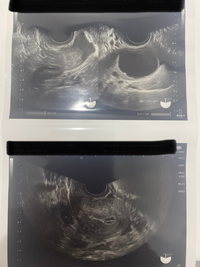

排卵後 卵胞 エコー 画像

排卵後 卵胞 エコー 画像のギャラリー

各画像をクリックすると、ダウンロードまたは拡大表示できます

超音波断層法検査とは耳では聞こえない高い周波数の音波を用いて、対象物を画像化する検査法です。 主に超音波を発信するプローベを腟内に挿入し、子宮内膜や卵胞 (卵子が入っている袋)の発育を観察する経腟超音波断層法を使用します。 排卵日を予測採卵前のエコーの個数と実際の採卵数が違うのはなぜですか? 掲載日:19年9月27日 卵子は卵巣の中の「卵胞」を満たしている「卵胞液」のなかにありますが、大きさは約01~02mmと小さいのでエコー画像で卵子を直接確認することはできません。 その